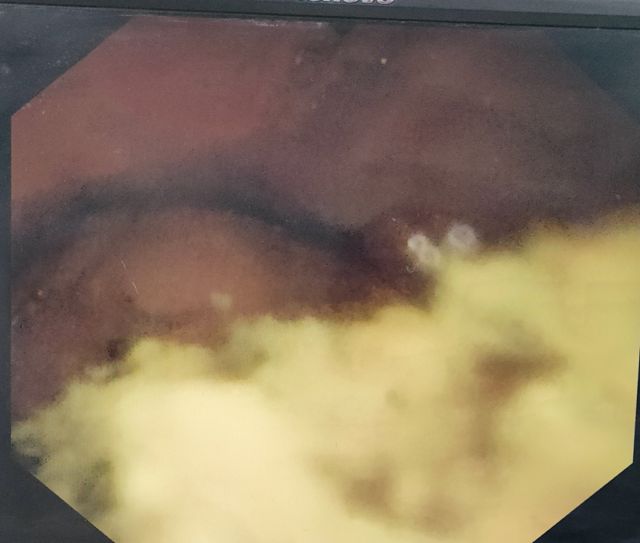

手术过程中,麻醉师刘合顺老师精心调控麻醉药物的剂量,确保患者在无痛状态下进行十二指肠镜操作,同时密切关注患者的心肺功能变化。由内镜科副主任谷渊操作十二指肠镜、科主任樊和明操作经口电子子母镜,双镜联合,精准探查结石位置,顺利取出胆管内的多发结石。整个治疗过程中,麻醉医生和内镜医生紧密合作,仅用了40分钟的时间,就将胆管内2块大结石及多发小结石全部取出,术中患者生命体征始终平稳。